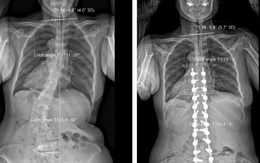

Sau mổ chữa còng, vẹo cột sống, một phụ nữ cao thêm 7cm, dáng người đi thẳng

Các bác sĩ Bệnh viện Trưng Vương TP.HCM vừa phẫu thuật thành công cho một phụ nữ tại Long An bị chứng còng, vẹo cột sống nặng suốt 15 năm.